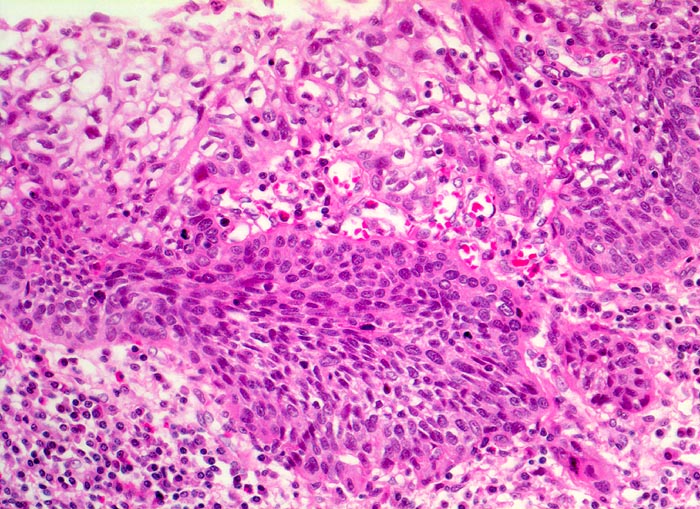

Morphologische Merkmale:

• Polypoides exophytisches Karzinom.

• Tumordurchbruch durch die Lamina muscularis mucosae in die Submukosa.

• Der Tumor bildet anastomosierende solide Zellstränge, die fokal im Zentrum verhornen.

• Tumorzellen mit reichlich glasigem eosinophilem Zytoplasma und scharfen Zellgrenzen mit stachelförmigen Interzellularbrücken. Stark vergrösserte, pleomorphe, hyperchromatische Zellkerne mit prominenten Nukleolen.

• Zwischen den Tumorzellsträngen desmoplastisches Stroma mit dichtem gemischtem Entzündungsinfiltrat.

• Präneoplastisch veränderte Mukosa im Randbereich des Karzinoms mit ausgeprägten Zellatypien in der gesamten Epithelbreite und zahlreichen Mitosen (Carcinoma in situ).